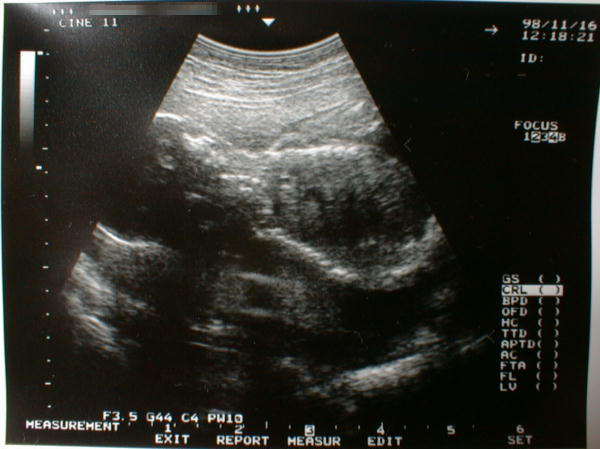

第22週に入った胎児の写真です。

(大きさは、分かりません・・・)

順調に育っているとの事でした。